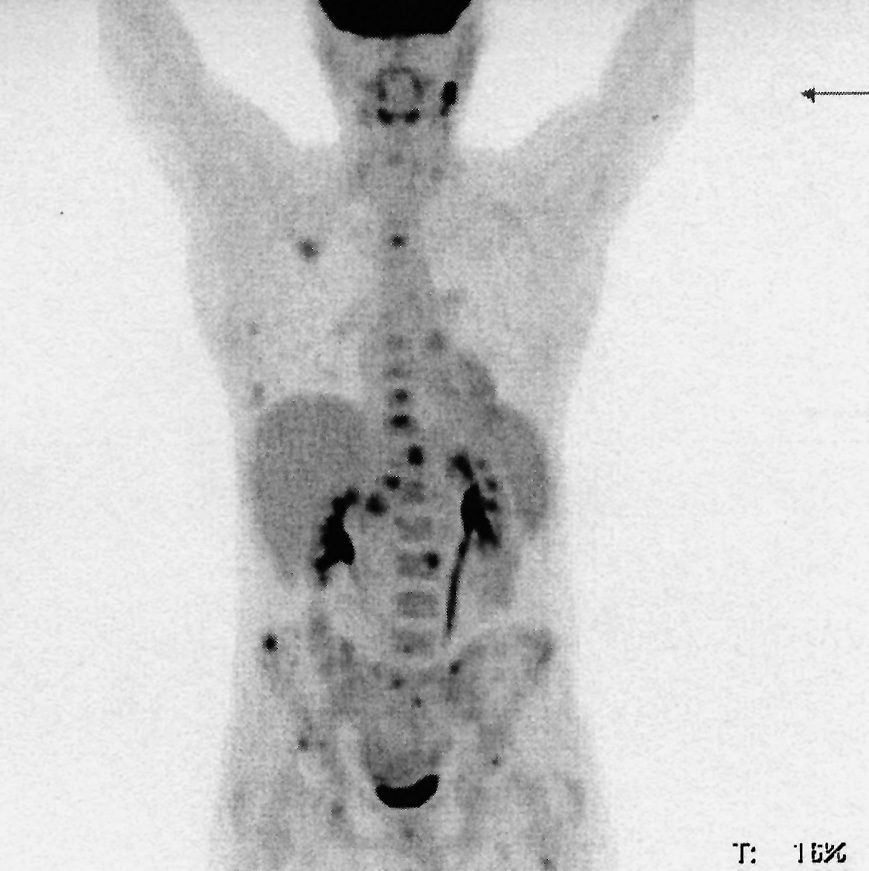

В июле 2017 г. в клинику МНИОИ им. П.А. Герцена – филиал ФГБУ «НМИЦ радиологии» обратился пациент 28 лет с жалобами на фебрильную лихорадку до 39°С, прогрессирующее снижение массы тела на 10 кг, увеличение надключичных лимфоузлов и ночную потливость. За полгода до обращения появились интенсивные боли в пояснично- крестцовом отделе позвоночника. Пациент наблюдался у невролога и уролога, проводилась антибактериальная и симптоматическая терапия. В июне 2017 г. было выполнено комплексное обследование, при котором выявлена генерализованная лимфаденопатия. Выполнена биопсия надключичного лимфоузла, при морфологическом и иммуногистохимическом исследовании установлен диагноз лимфомы Ходжкина, нодулярный склероз 1-го типа [крупные одно- и многоядерные клетки CD45 негативны, в них выявляется положительная реакция с CD15, CD30 (мембранное, цитоплазматическое и пятнистое в зоне аппарата Гольджи окрашивание), РАХ5 (слабая ядерная реакция)]; CD20-, CD3-, EBV-негативные. Основная масса мелких лимфоидных клеток CD3 положительна, в умеренном количестве сохранены CD20-положительные В-лимфоидные клетки. На ПЭТ-КТ перед началом лечения выявлены генерализованная лимфаденопатия по обе стороны диафрагмы (SUVmax до 13), вовлечение селезенки и множественные очаги повышенного накопления радиофармпрепарата в костях без структурных изменений по КТ (рис. 1). С учетом распространенной стадии заболевания больной отнесен к группе неблагоприятного прогноза.

Рис. 1. ПЭТ-КТ в дебюте заболевания (поражение правых надключичных, множественных внутригрудных, забрюшинных, подвздошных, паховых лимфоузлов, селезенки, проксимальных диафизов плечевых костей, левой боковой массы крестца, крыла правой подвздошной, нижней ветви левой лонной кости, шеек бедренных костей).